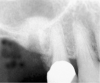

Sinus Floor Elevation in a Socket

The sinus floor elevation technique can be used when a tooth is extracted and there is not enough bone height to support an immediate implant (Figure 8, Figure 9 and Figure 10, Figure 11).32

Figure 8  At site No. 13 the second bicuspid had a hopeless prognosis; it was to be extracted and replaced with an implant after a transcrestal sinus floor elevation.

Figure 8

Figure 9: After the extraction, a 2.1-mm twist drill was used to drill within 1 mm of the subantral floor. A guide pin was placed and a radiograph was taken to ascertain if the drill stopped within 1 mm of the subantral floor.

Figure 9